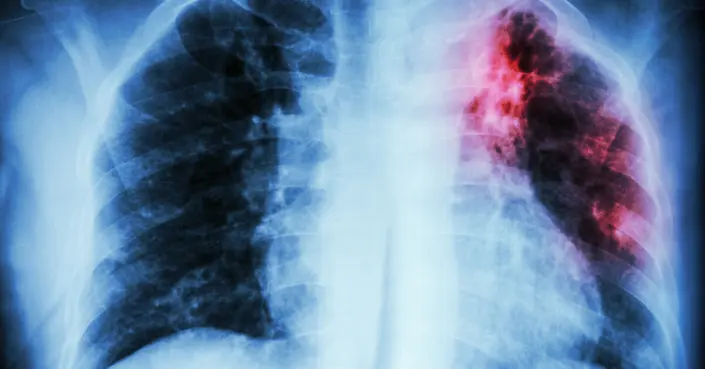

دور الصور الشعاعية في التشخيص

تُعد الصور الشعاعية، مثل الأشعة السينية (X-ray) والأشعة المقطعية (CT scan)، أدوات دعم مهمة جدًا في تشخيص السل الرئوي، حيث تُساعد في الكشف عن التغييرات التي تطرأ على الرئتين بسبب العدوى.

علامات شعاعية للعدوى النشطة

في معظم المرضى الذين يُعانون من العدوى النشطة أو المُعاد تنشيطها، تُظهر صور الأشعة الرئوية اعتلالات واضحة، حتى وإن لم تكن الأعراض بارزة. من هذه الاعتلالات:

1. ارتشاحات رئوية في القسم القمي الخلفي: تظهر غالبًا في الجزء العلوي والخلفي من الفص العلوي للرئة، وذلك في حوالي 80-90% من الحالات.

2. علامات أخرى غير نمطية مثل: تضخم الغدد اللمفاوية النقيرية، وتجاويف (كهوف) في المناطق الوسطى والسفلية من الرئة.